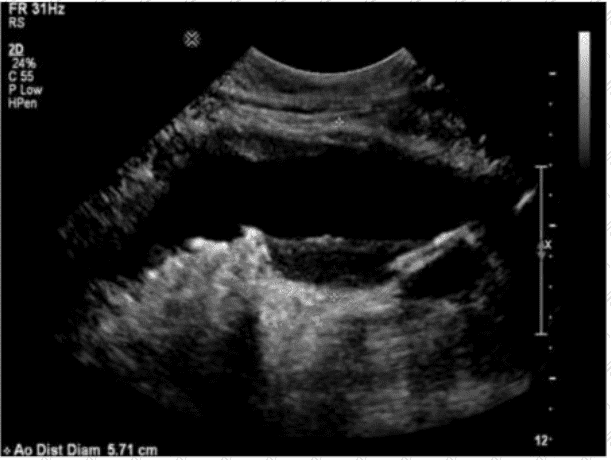

Which sonographic finding is most consistent with this image of the abdominal aorta?